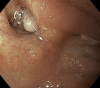

Endoscopic closure of a refractory enterocutaneous fistula by use of a fistula plug with fixation and mucosal oversewing